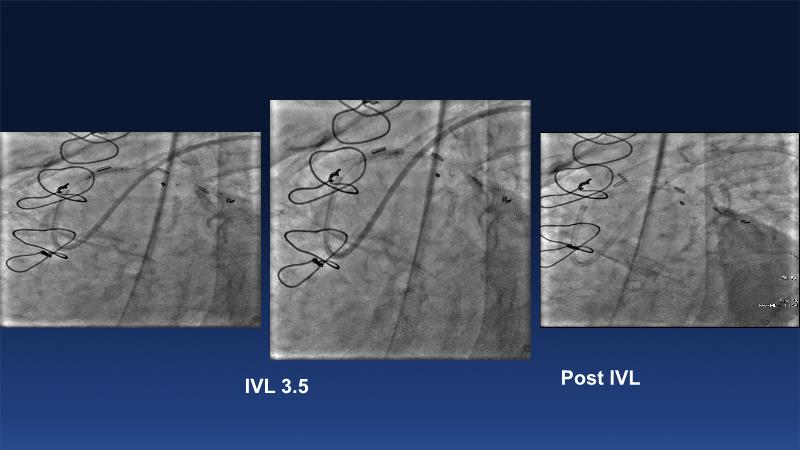

Over the last five years, we have learned that there is a new tool for treating calcium, the greatest enemy of interventional cardiology, which can take various forms: intravascular lithotripsy. In this session, look at how to master this technique in different scenarios, from eccentric calcified lesions to left main bifurcations.

- To understand the mechanism of action of intravascular lithotripsy (IVL) for the treatment of calcified lesions

- To uncover practical tips and techniques for IVL in challenging calcified lesions: eccentric calcified lesions